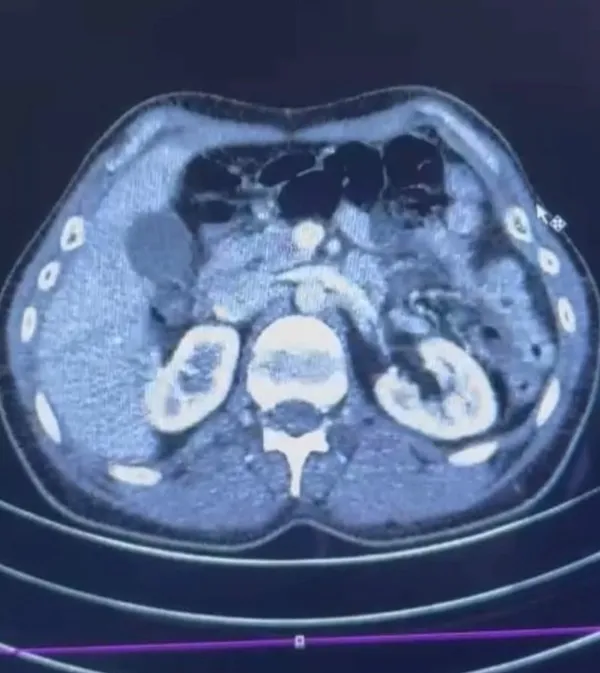

Şüphelilerden S.C. ve R.B.C'nin Kayseri Şehir Hastanesi'nde yapılan iç beden muayenesinde mide kısımlarında gizlenmiş 50 adet kapsül şeklinde toplam 554 gram uyuşturucu madde tespit edildi. Uyuşturucular yapılan cerrahi müdahale ile çıkartıldı. Olayla ilgili başlatılan soruşturmada, S.C., R.B.C. ve G.M. adlı şüpheliler, "Uyuşturucu Madde Ticareti Yapmak" suçlamasıyla gözaltına alındı.